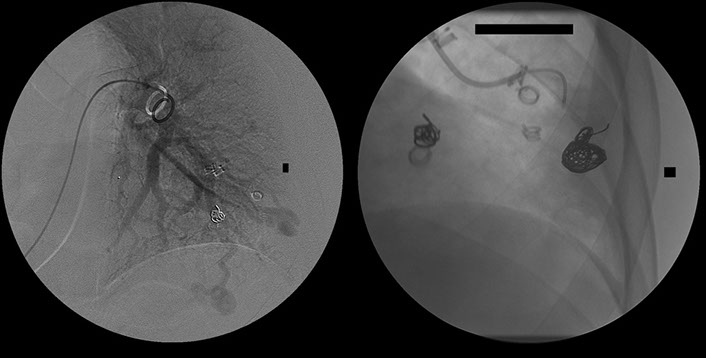

Lady with transient ischaemic attacks. Note the rounded density lateral to the right breast.

Which in the lateral projection can be clearly seen projected over the heart.

This turned out to be another AV malformation which was occluded by multiple coils. Note the post embolisation picture in the bottom right corner.